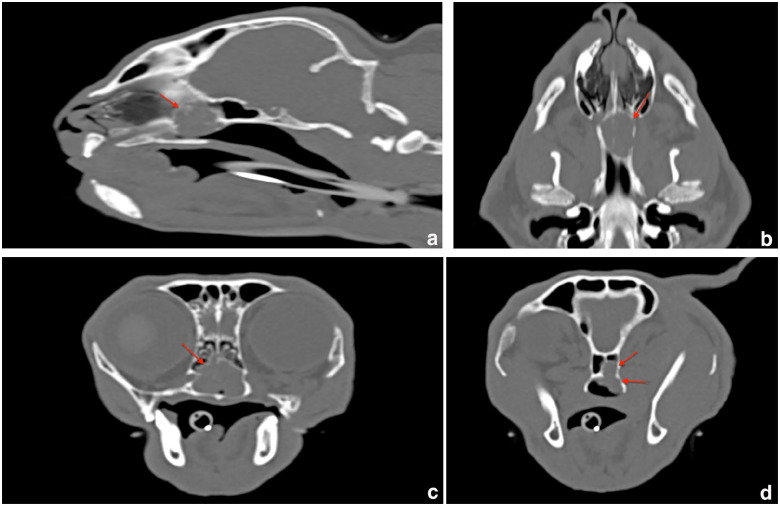

Case summary: A 10-year-old castrated male crossbreed Birman cat was presented for respiratory difficulties, nasal discharge, dysphagia and wheezing. An obstructive nasopharyngeal mass invading the caudoventral nasal cavity and the left sphenoid sinus was observed on a CT scan. Surgical treatment via a ventral rhinotomy and curettage was performed. Histopathology revealed an adenocarcinoma with tubulotrabecular architecture. The cat's clinical signs significantly improved postoperatively. After 10 months, a recurrence was documented and a second surgical procedure was performed that allowed the patient to live an additional 6 months without clinical signs and an overall survival time of 19 months after first presentation.

Relevance and novel information: This case report describes a nasopharyngeal adenocarcinoma treated by ventral rhinotomy in a cat. To our knowledge, there is only one other report describing this surgery on a nasal adenocarcinoma in a cat. The tomodensitometric, endoscopic and unusual histological appearance of the mass are reported. The prognosis after surgical removal of nasal adenocarcinomas in cats is only sparsely documented. This case demonstrates that ventral rhinotomy might be considered if first-line treatment is declined.